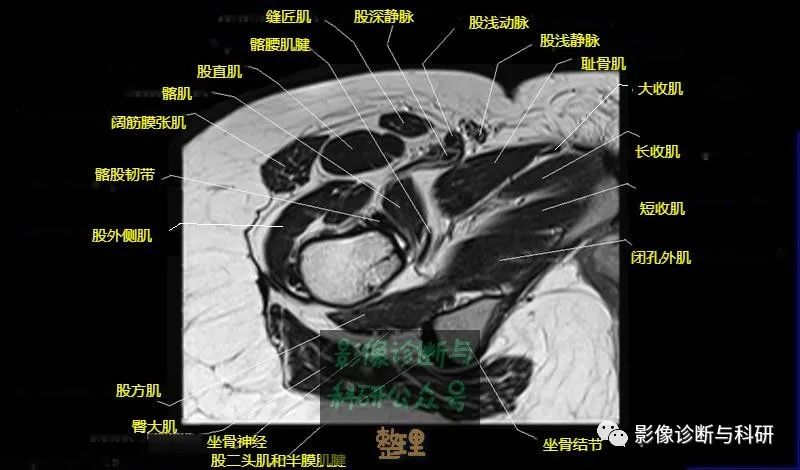

大腿肌配布于股骨周围,分前、后和内侧三群

前群

位于大腿前面,有缝匠肌和股四头肌。

作用:伸膝关节,股直肌带可屈髋关节。

内侧群

位于大腿内侧,共5块,其中股薄肌位于最内侧;另4块分三层,浅层靠外上方为为耻骨肌,下方为肌长收肌。长收肌深面是第二层的肌短收肌。第三层是强有力的大收肌。这一群肌均起自耻骨支和坐骨支,除股薄肌止于胫骨上端内侧外,其余各肌都抵止在股骨粗线。

作用:大腿内收。

后群

位于股骨后方,包括股二头肌、半腱肌和半膜肌。

作用:屈膝关节、伸髋关节。